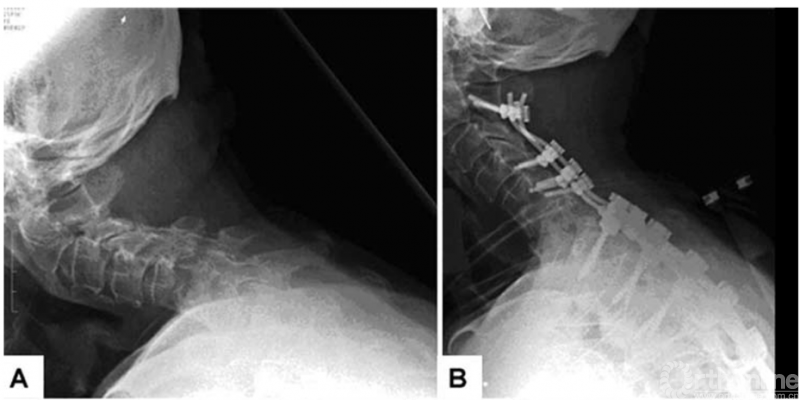

2.2.1 C7-T1 伸展性截骨

C7-T1伸展性截骨适用于颈胸段单纯后凸畸形患者。手术时切除C7全部椎板、C6椎板下半部分及T1椎板上半部分,扩大椎间孔,切除部分椎弓根;调整Mayfield头架,伸展患者颈部直至C7腹侧骨折完成矫形;双侧置入预弯连接棒,抱紧加压,闭合截骨面完成矫形。此术式前纵韧带完整性遭到破坏,椎体易发生脱位;食管和气管易发生移位,造成吞咽和呼吸困难;截骨椎前方椎间隙易形成假关节。